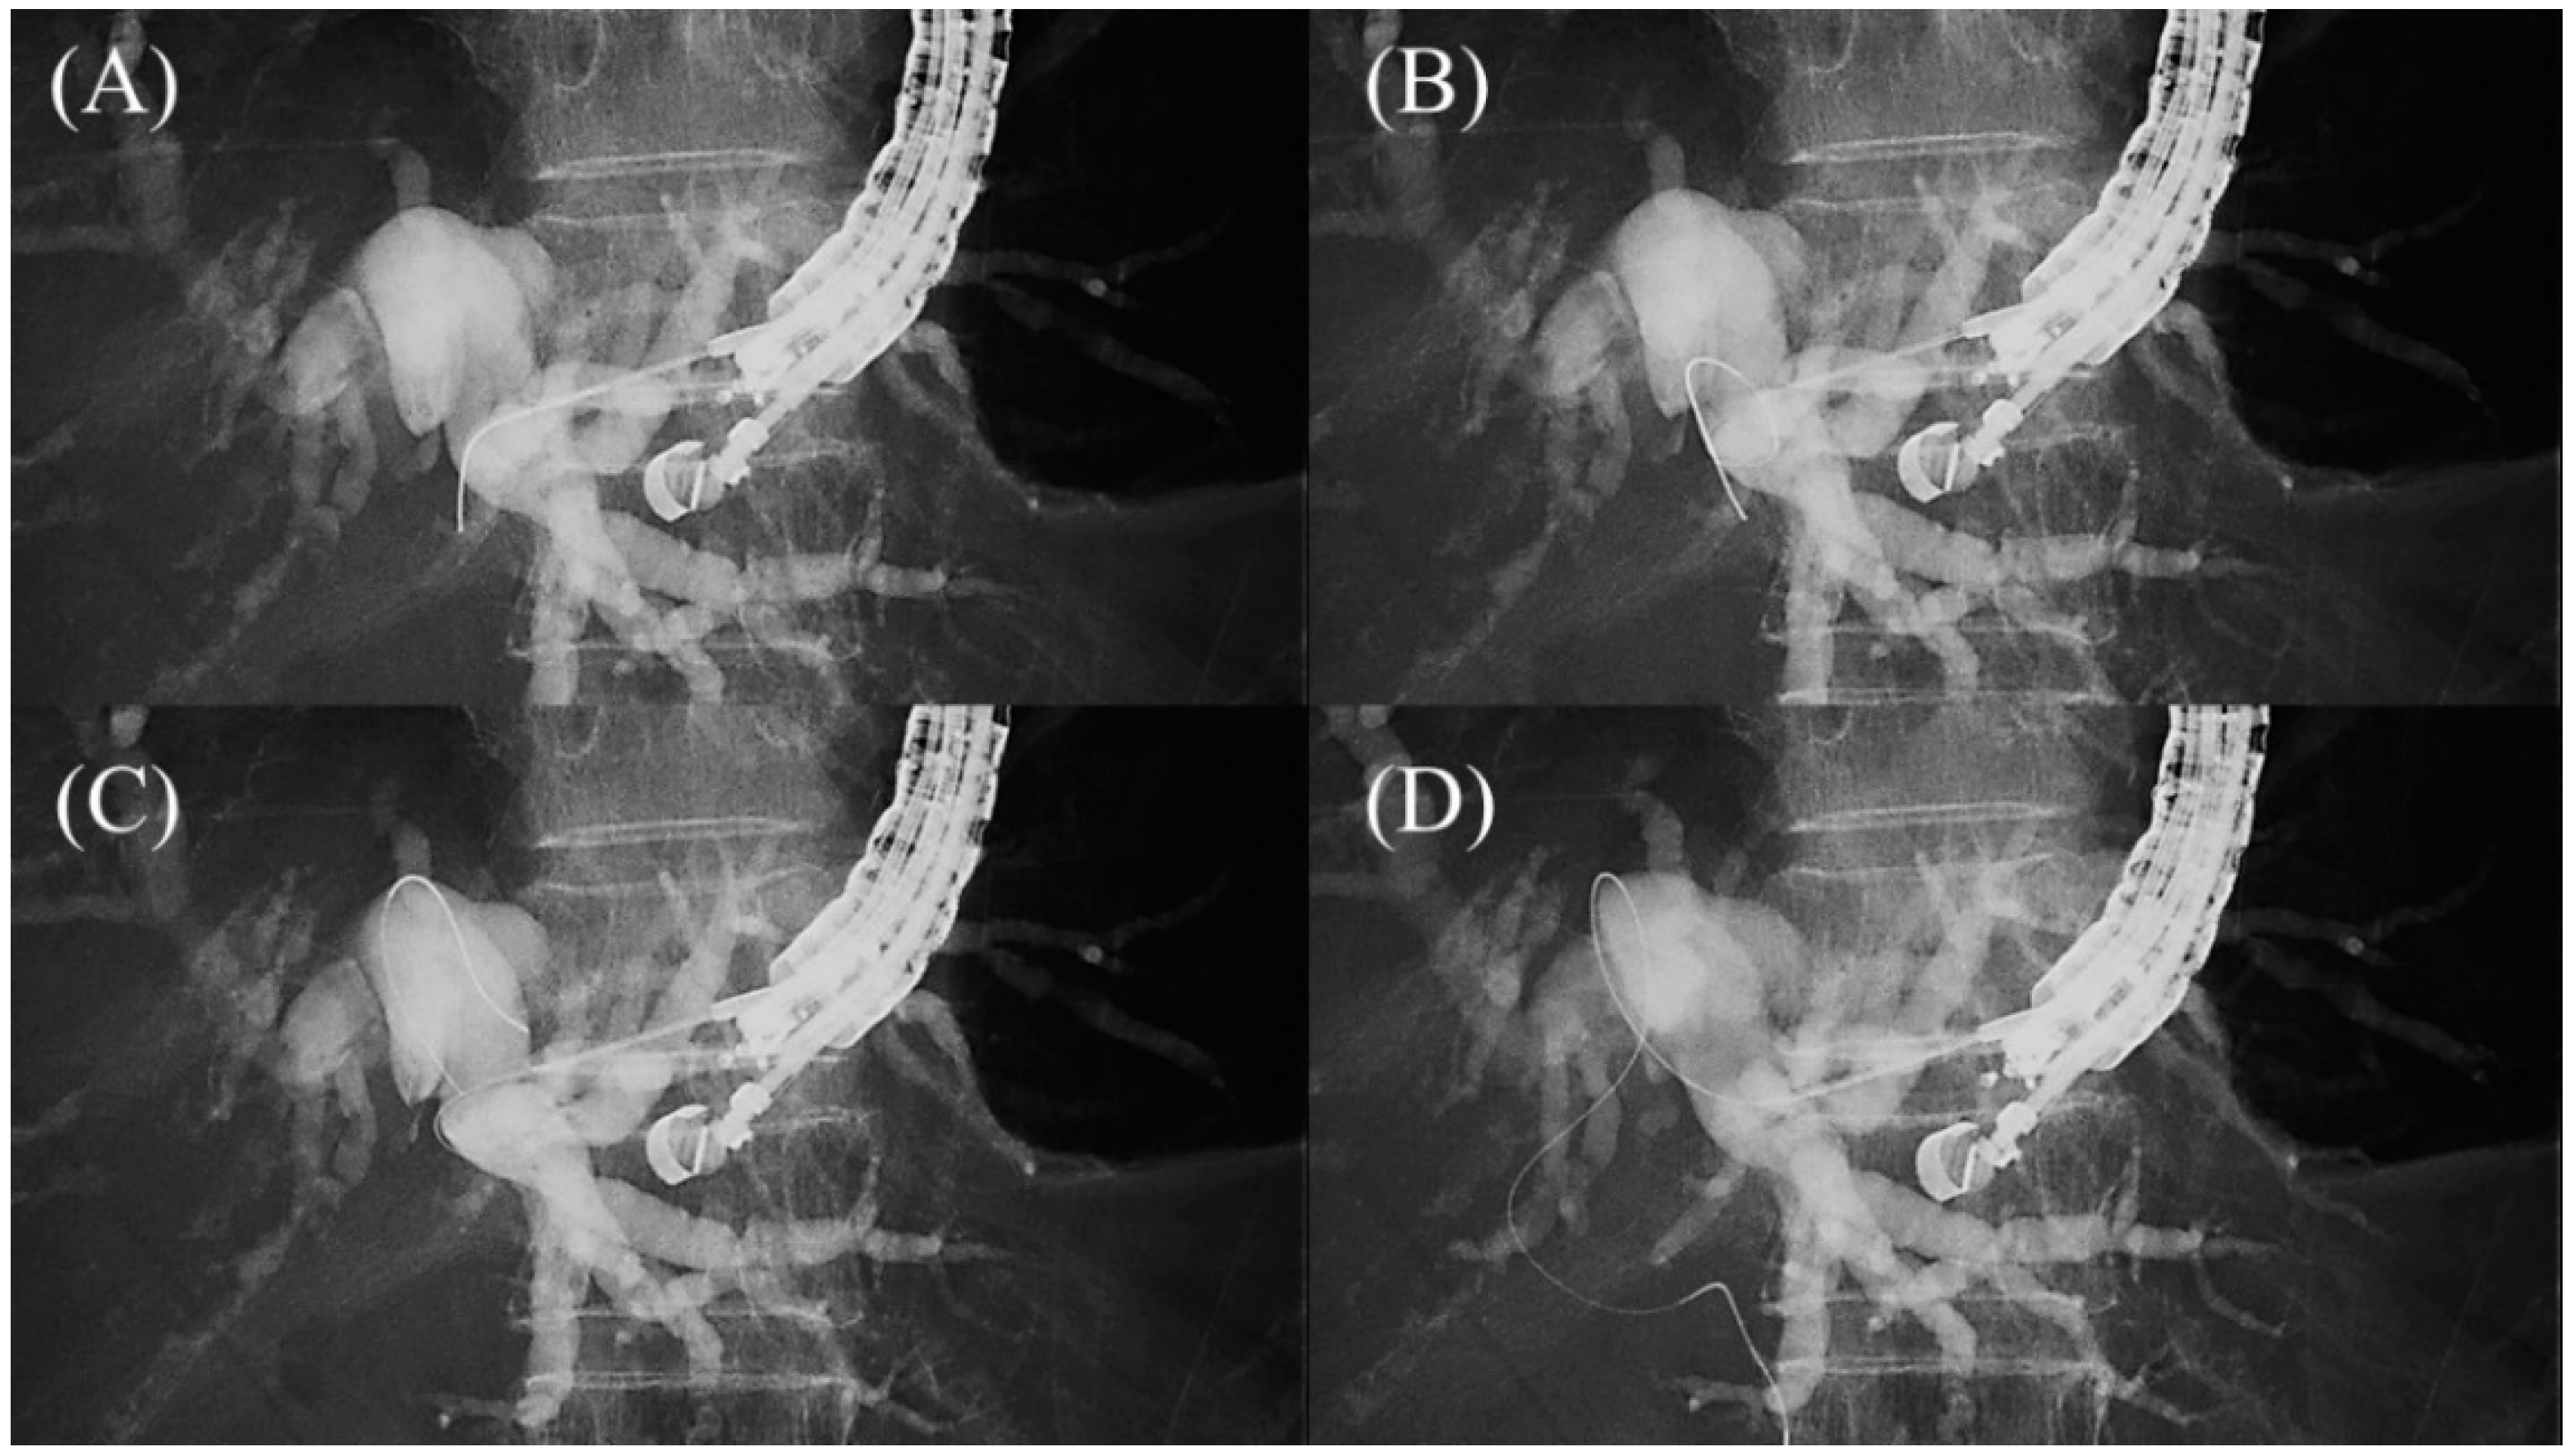

The guidewire is advanced through the needle, and once it enters the bile duct, it is slowly and carefully advanced with gentle rotation to guide it toward the hilar region. If the guidewire is unintentionally advanced to the peripheral side, the “Loop technique” should be attempted first. Push the guidewire with rotation, and when the tip of the guidewire is caught on a lateral branch (Figure 10A), push the guidewire further. Since the tip of the guidewire is fixed, the body of the guidewire will bend with the pushing force and form a loop (Figure 10B). If the loop is facing the hilar region, the guidewire can be advanced to the hilum by pushing further (Figure 10C,D). If the “Loop technique” fails, the “Moving scope technique” is an alternative to change the direction of the guidewire, where pushing the scope while turning the large wheel upward may change the direction of the needle to the cranial side, allowing the guidewire to proceed toward the hilum [39] (Figure 11A–C).

Figure 10.

Loop technique for redirection of a guidewire. If a guidewire is unintentionally advanced to the peripheral side, push the guidewire with rotation. When the tip of the guidewire is caught on a lateral branch (A), the guidewire will bend and form a loop by pushing force (B). If the loop is facing the hilar region, the guidewire can be advanced to the hilum by pushing further (C,D).